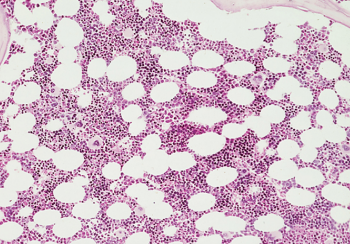

Normal

**Bone Marrow**

Hyperplastic

Hypoplastic